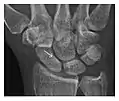

High-energy trauma fractures

Occult osseous injuries may result from a direct blow to the bone by compressive forces of adjacent bones against one another or by traction forces during an avulsion injury. Lesions in the tibial plateau, hip, ankle, and wrist are often missed. In a tibial plateau fracture, any disruption of the posterior and anterior cortical rims of the plateau should be sought. Impaction of subchondral bone will appear as an increased sclerosis of the subchondral bone (Figure 1). In the hip, posterior acetabular fractures also present subtle radiographic findings. The acetabular lines should then be carefully examined keeping in mind that the posterior rim, which is harder to see on X-rays, is more frequently fractured than the anterior rim (Figure 2). In the wrist, detection of carpal bone fractures is often challenging, with up to 18% of scaphoid fractures radiographically occult. Carpal fractures, especially the scaphoid, are associated with the risk of avascular necrosis. In apparently normal wrist radiographs from symptomatic patients, if there is history of a fall on an outstretched hand with pain in the anatomic snuffbox, suggesting scaphoid injury, the initial examination with posteroanterior, lateral, and pronation oblique views must be complemented by other specific views such as supination oblique and the "scaphoid" view A careful examination of cortices for evidence of discontinuity or offset and cancellous bone for lucency is necessary (Figure 3).[1]

Figure 3: A 26-year-old man presenting with wrist pain after being assaulted. (a) Initial anteroposterior radiograph shows a subtle linear lucency within the scaphoid extending to the scaphocapitate articular surface that was overlooked (arrow). (b) Initial "scaphoid" view was negative. (c) Followup anteroposterior radiographs, 12 days later, shows obvious scaphoid fracture (arrows).[1]

Triquetral fracture usually occurs on the dorsal aspect by impingement from the ulnar styloid or avulsion of strong ligamentous attachment. The dorsal avulsion fracture or "chip fracture" appears as a small bony fragment on the dorsal aspect of the triquetrum and is best detected on the lateral view(Figure 4). When radiography is negative in patients with high suspicion of a fracture, both MRI and MDCT will be of value. However, it has been shown that MRI is superior for detecting trabecular fractures in carpal bones.

a

b

Figure 4: Dorsal triquetral fracture of the left wrist in a 30-year-old man after a trauma. (a) Anteroposterior radiograph shows a normal appearance. (b) Lateral radiograph of the same wrist demonstrates a chip fracture off the dorsal aspect of the triquetrum (arrow).[1]